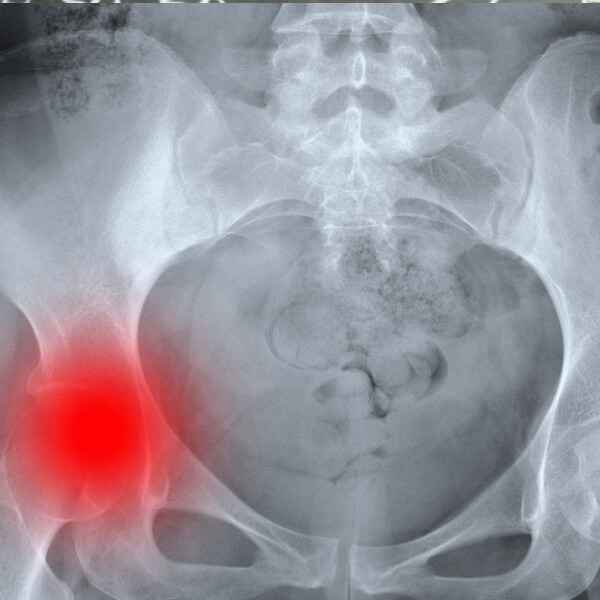

La fractura de cadera es una de las patologías más frecuentes en el anciano. Además, con grandes repercusiones sociales, sanitarias y económicas, se prevé que su incidencia vaya en aumento en los próximos años. De ahí la importancia de su prevención, en la que la enfermería tiene un papel protagonista. De hecho, el éxito de su tratamiento reside, principalmente, en su prevención primaria, pero también en la reducción de complicaciones.

Tema I. Epidemiología.

Tema II. Concepto y Generalidades.

Tema III. Etiología.

Tema IV. Factores de riesgo de fractura de cadera.

Tema V. Diagnóstico.

Tema VI. Clasificación o tipos de fractura.

Tema VII. Presentación clínica y características de los pacientes con fractura de cadera.

Tema VIII. Tratamiento.